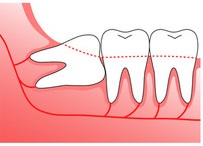

歯ぐきの中に完全に埋まってしまっていて表面には出ていない、見えない状態です。親知らずがある部分が腫れている、痛みがある、他の歯や顎関節への影響がある場合は抜歯を検討する必要があります。水平埋伏智歯

親知らずが横向きに生えている状態です。横向きに生えているために歯を圧迫して歯並びに影響を与えたり、歯茎などの腫れや痛みの原因になることがあります。年齢を重ねたり、歯磨きがきちんとできていないとより症状が出やすくなるので、早めに抜歯をすることをお勧めしています。

親知らずが横向きに生えている状態です。横向きに生えているために歯を圧迫して歯並びに影響を与えたり、歯茎などの腫れや痛みの原因になることがあります。年齢を重ねたり、歯磨きがきちんとできていないとより症状が出やすくなるので、早めに抜歯をすることをお勧めしています。半埋伏智歯

歯ぐきから親知らずが一部だけ出ている状態です。周りの歯への影響、むし歯や歯周病のリスクが高くなります。歯科医師と相談をして抜歯をすることを推奨します。

歯ぐきから親知らずが一部だけ出ている状態です。周りの歯への影響、むし歯や歯周病のリスクが高くなります。歯科医師と相談をして抜歯をすることを推奨します。